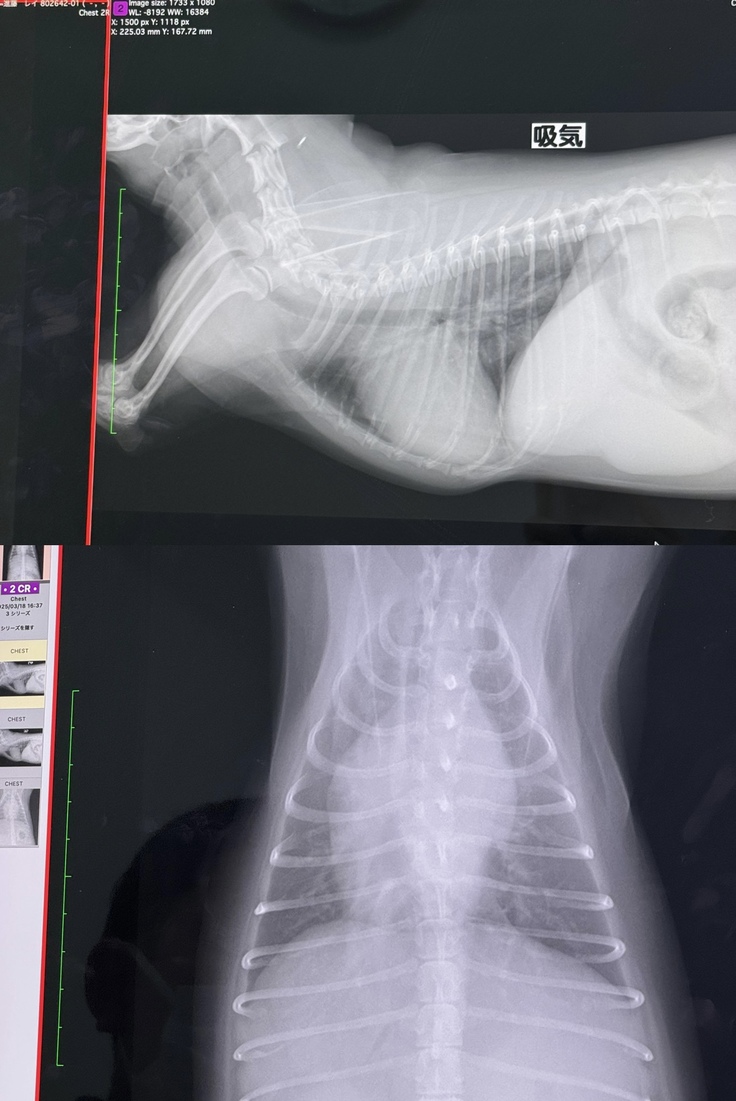

▶︎レントゲン写真

心臓が大きく、肥大してしまってます。

▶︎二度目の肺水腫のレントゲン画像

左側肺水腫 右側正常な時

左側の上の部分が右側より白くなっています。